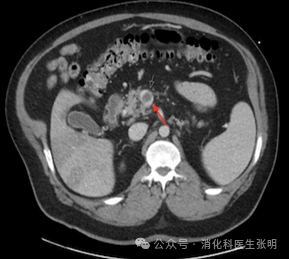

门静脉左支内的血栓

图片

门静脉主干内的血栓